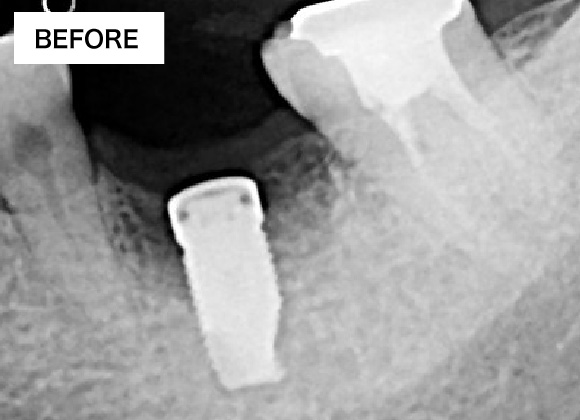

BEFORE・AFTER